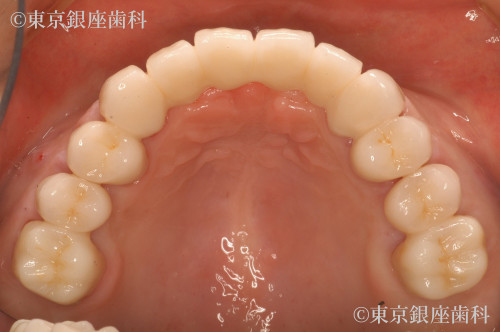

After

ワンデイインプラントで審美を回復

上部は審美治療を行い、下部はワンデイインプラントを行った